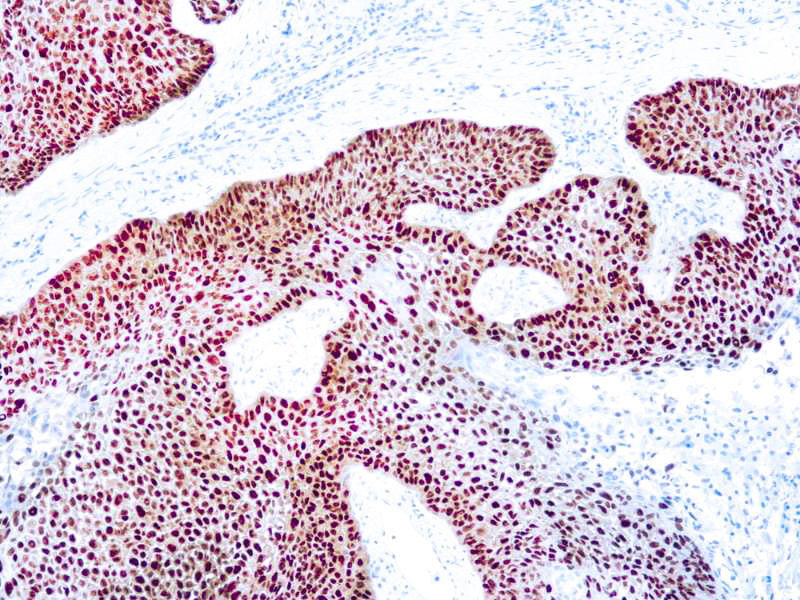

p63

p63 is a homolog of the tumor suppressor p53, it is identified in basal cells in the epithelial layers of a variety of tissues, including epidermis, cervix, urothelium, breast and prostate. p63, vital for the development of the prostate and selectively expressed by normal prostate basal cells, has been shown to be a promising complementary basal cell specific marker to High Molecular Weight-Cytokeratin (HMW-CK), for the differential diagnosis of benign prostatic lesions and prostatic carcinoma. p63 has also been shown to be a sensitive marker for lung squamous cell carcinomas (SqCC), with a sensitivity of ~90% . Specificity for lung SqCC, vs. lung adenocarcinoma (LADC), is approximately 80. In breast tissue, p63 has been identified in myoepithelial cells of normal ducts.